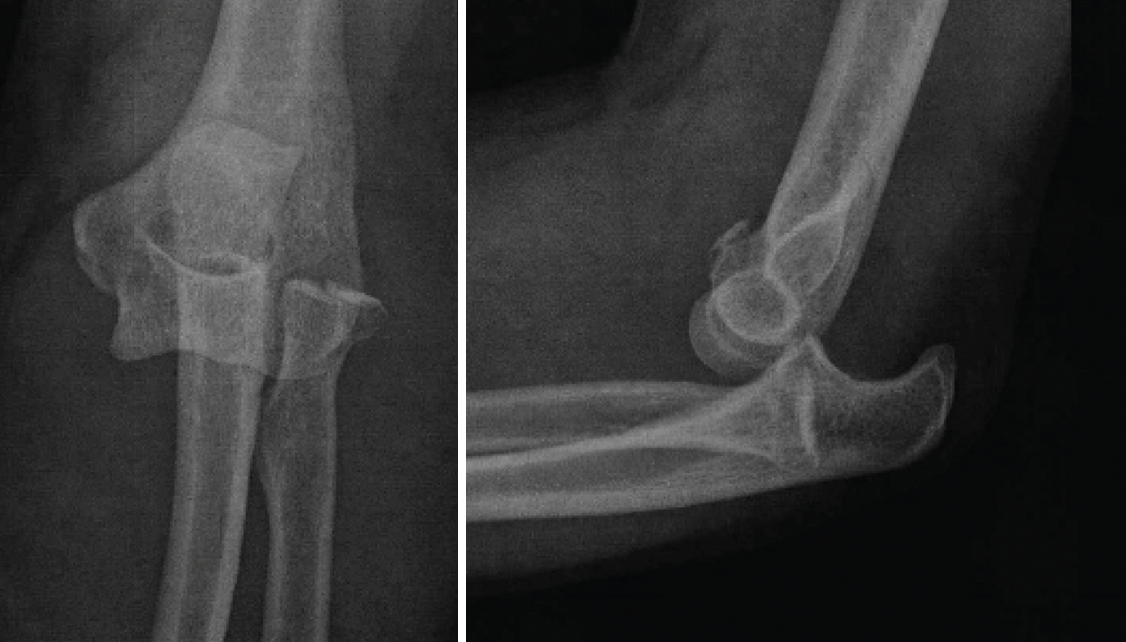

Este patrón de inestabilidad compleja de codo se caracteriza por una luxación posterior de codo asociada a 3 lesiones principales (Figura 14):

• Fractura de la cabeza del radio.

• Rotura del LCL.

• Fractura de la coronoides.

Figura 14. Tríada terrible de codo derecho donde puede apreciarse en las imágenes de tomografía computarizada la fractura de la cabeza del radio, la fractura de la coronoides y la subluxación posterolateral de la ulnohumeral.